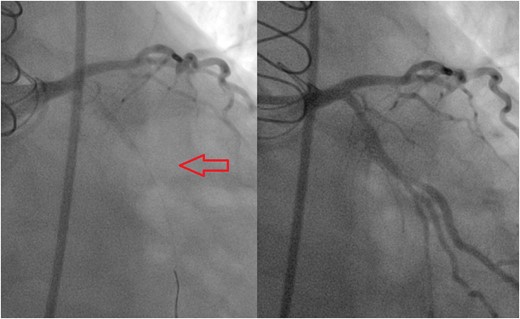

On the morning of surgery, the patient complained of acute, severe chest discomfort and was diaphoretic and pale. EKG demonstrated new ST depressions in V1–V4 (Fig. 1). CT coronary angiography was considered, however, given an evolving acute coronary syndrome (ACS), the decision was made to proceed for emergent coronary angiography, understanding the risks of possible iatrogenic embolization, but the benefit of rapid revascularization. The time to revascularization following lesion identification on CT and subsequent re-operative cardiac surgery was felt to be time prohibitive. Angiography revealed a 100% left circumflex ostial occlusion (Fig. 2). The saphenous vein to the diagonal graft was widely patent and no additional lesions were identified. The presumed etiology of the new circumflex occlusion was a septic embolism secondary to prosthetic valve endocarditis. After discussions with the cardiac surgeon, referring cardiologist and patient, we felt that a hybrid strategy of attempted percutaneous coronary intervention with aspiration thrombectomy followed by open surgical valve replacement provided the optimal benefit/risk profile. Aspiration thombectomy was performed with an Export® AP thrombectomy catheter (Medtronic Inc., Minneapolis, MN) retrieving a substantial amount of organized material concerning for thrombo-vegetation (Fig. 3). After two passes of the aspiration catheter TIMI 3 flow was restored (Fig. 3), ST depressions resolved, and he experienced significant improvement in his chest pain.

Angiogram before (left) and after (right) aspiration thrombectomy demonstrating excellent angiographic result.